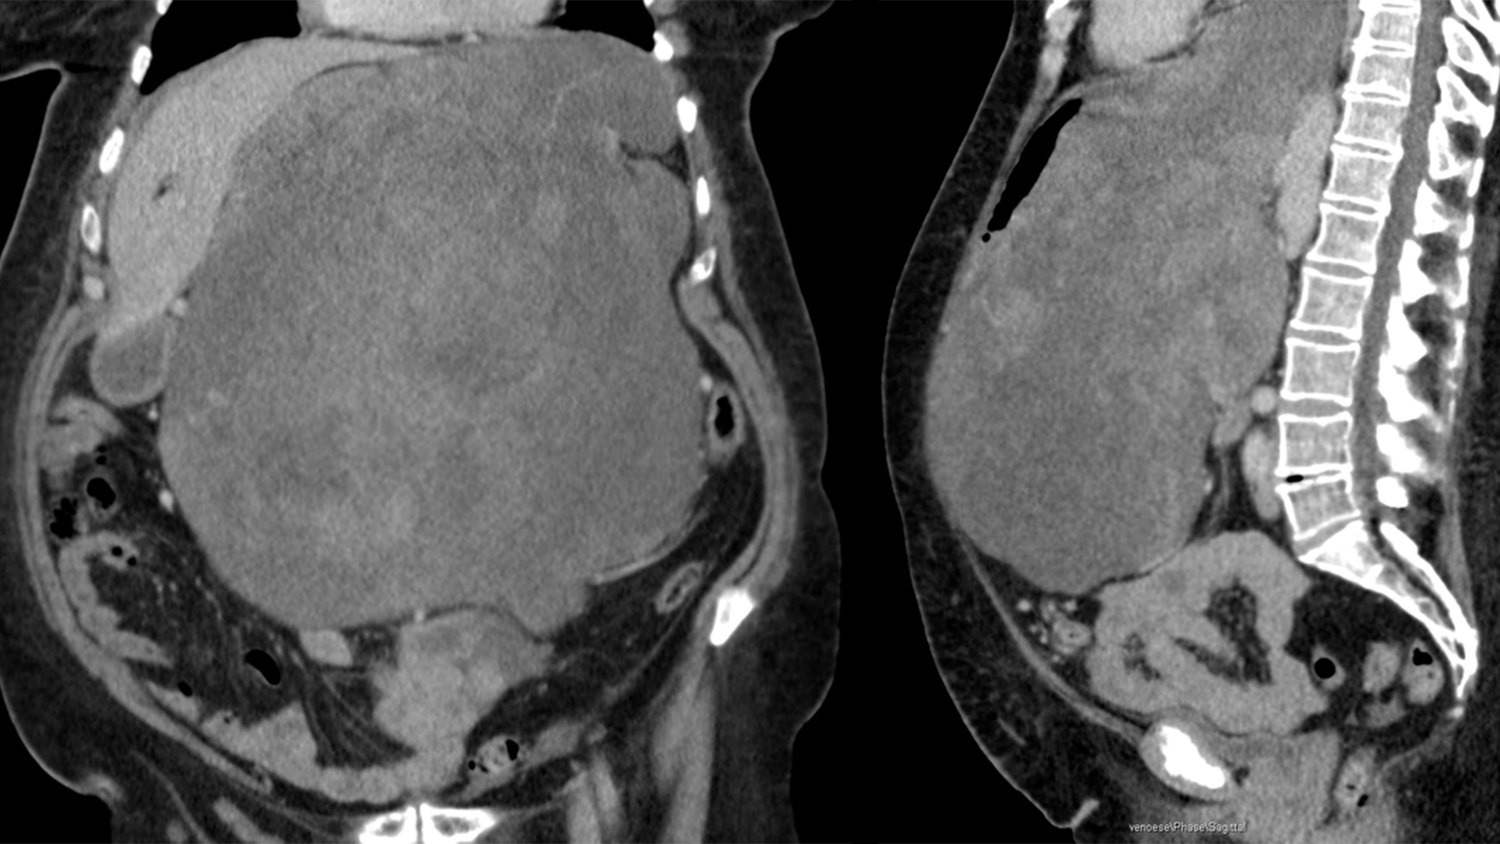

Beim Blick auf die CT-Bilder mussten die Mediziner gleich zweimal hinschauen. Denn der Tumor, den sie auf dem Bild sahen, war derart groß, dass die Fachleute es kaum glauben konnten. Im Bauch der 65-jährigen Patientin hatte sich ein 8,5 Kilogramm schwerer Tumor breitgemacht, der Leber und Magen sowie den Darm an den Rand der Bauchdecke drängte. Im Klinikum Bremen-Mitte hat Prof. Dr. Hüseyin Bektas diesen rekordverdächtigen Tumor nun Anfang April in einer aufwendigen Operation mit seinem Team entfernt.

Da der Tumor vom Magen aus auch schon Speiseröhre und Bauchspeicheldrüse befallen hatte, mussten diese teilweise – die Milz sogar komplett – mitentfernt werden. Von dem großen Eingriff musste die Patientin sich zunächst erholen, am nächsten Tag folgte dann die Rekonstruktion des Magen-Darm-Trakts. Dabei wurde aus dem übriggebliebenen Magen ein Magenschlauch gebildet, der an die Speiseröhre angeschlossen wurde.